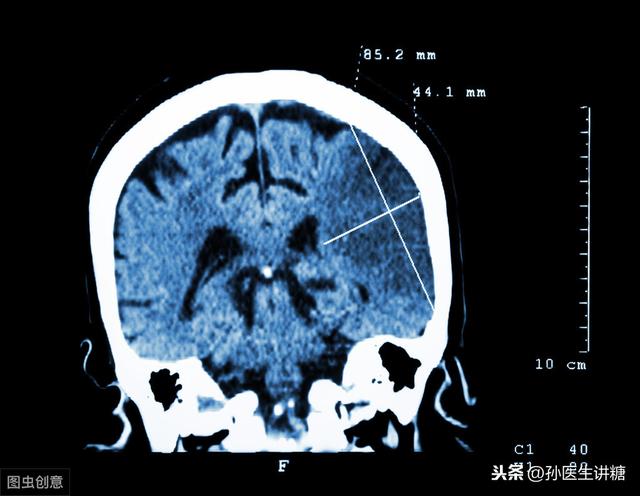

2型糖尿病は過体重・肥満と密接な関係がある。肥満患者の病因は主にインスリン抵抗性であり、その結果、脂肪細胞はインスリンに鈍感になり、一方では、しばしば脂質異常症、インスリン抵抗性を形成しやすいラジカル脂肪酸の増加を伴う。血糖値の上昇は全身の血管に影響を及ぼし、血管硬化、血流の低下、血小板凝集の増加、血栓の形成、脳血管の閉塞などをもたらし、いくつかの要因が相乗的に作用して最終的に脳血栓症を引き起こす。軽症の場合は患者のQOLに影響を及ぼし、重症の場合は生命を脅かす。

さらに深刻なことに、大量の脂肪も血管に入り込み、血管壁の脂肪変性が起こり、血管の正常な組織構造を破壊し、脂肪の変性がプラークの塊を形成するとき、血管は狭くなり、硬くなり、壊れやすくなり、閉塞の破裂がいつでも起こる可能性があり、これが心・脳血管疾患の発生の根本原因である。